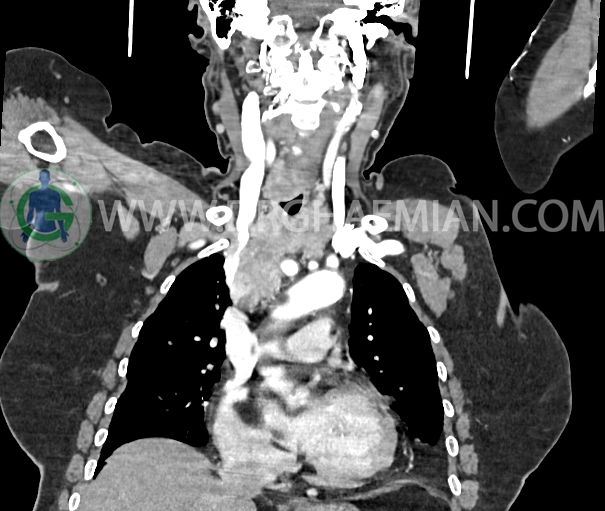

در سی تی اسکن اسپیرال از گردن و ریه و مدیاستن با تزریق (مولتی دیدکتور 16 با مقاطع ظریف و بازسازی های ساژیتال و کرونال) :

تصویر توده نسج نرمی با enhancement هتروژن و حدود لوبوله به ابعاد 25x55x93mm با شروع از خلفی فضای ساب گلوت (ابتدای تراشه) و امتداد در بستر تیروئید ومدیاستن قدامی دیده می شود

توده مذکور به درون تراشه گردنی bulge شده و موجب narrowing تراشه شده و به نظر می رسد invasion به لومن وریدهای براکیوسفالیک دو طرف و SVC دارد .

وریدهای واریسی متعدد در اطراف مهره ها در مجموع می تواند SVC syndrome را مطرح کند.

ندول های round متعدد به صورت پراکنده در فیلد ریه ها مشهود است که مطرح کننده متاستاز ریوی می باشد